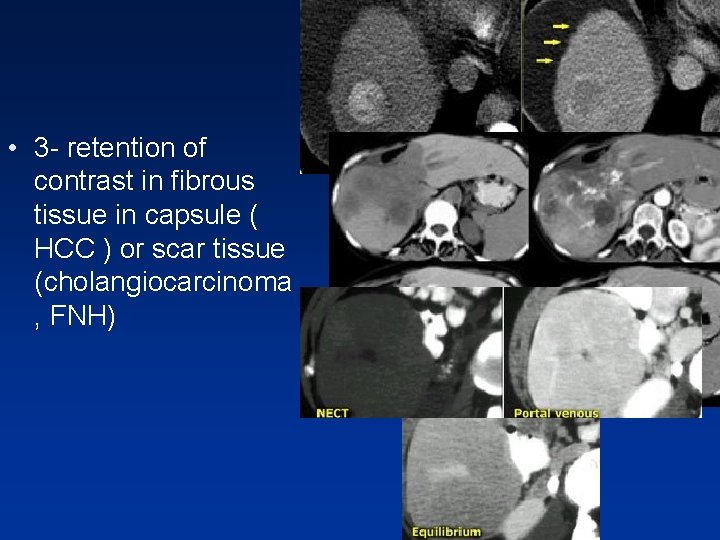

• This phase can be valuable if you are looking for: 1 - fast tumor washout in hypervascular tumors 2 - retention of contrast in blood pool like in hemangioma 3 - retention of contrast in fibrous tissue in capsule ( HCC )or scar tissue ( cholangiocarcinoma or FNH )

• 3 - retention of contrast in fibrous tissue in capsule ( HCC ) or scar tissue (cholangiocarcinoma , FNH)

Relative hyperdense lesions in the delayed phase • Fibrous tissue that’s well organized and dense is very slow to let iodine or gadolinium in. • Once contrast gets in however, it is equally slow to get back out in the equilibrium phase. • So when the normal liver parenchyma washes out, the fibrous component of the tumor will look brighter than the background liver tissue.

• Small cholangiocarcinoma not visible in portal venous phase , but seen as relative hyperdense lesion in the equilibrium phase.